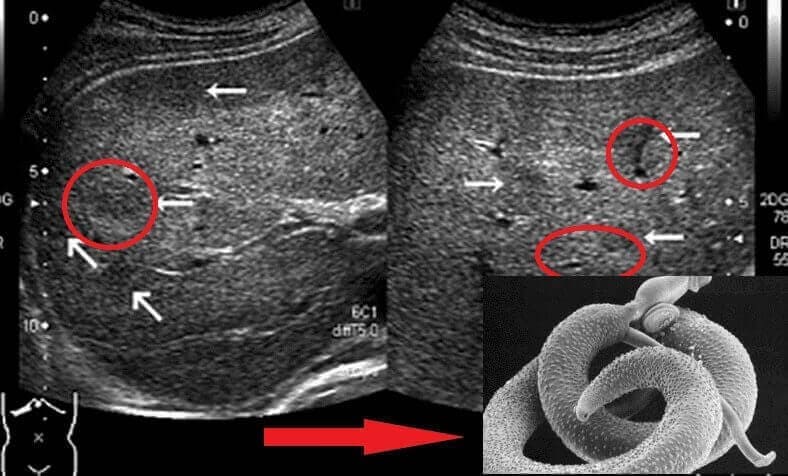

En la autopsia encontraron parásitos repartidos por todo su cuerpo: en el estómago, en el hígado, incluso en el corazón… ¡Fue terrible!

Los análisis confirmaron la presencia de parásitos. El doctor me dijo que era algo muy común, "incluso en gran parte de la población chilena". El síntoma más evidente: los papilomas.

Investigando en internet descubrí que algunos parásitos son realmente difíciles de eliminar: pueden adherirse a los órganos y, aunque mueran, sus huevos sobreviven. Después de unas semanas, esos huevos vuelven a eclosionar y se forma un círculo vicioso.

Existen decenas de clases de parásitos, algunos son largos gusanos que pueden detectarse con más facilidad, pero otros son microscópicos y viajan por el torrente sanguíneo, intoxicando lentamente tu cuerpo con sus toxinas.

– Efectivamente. Los papilomas suelen ser un marcador muy fiable de la infestación parasitaria. Estudios recientes lo confirman. Pero los parásitos no solo provocan papilomas. Segregan toxinas muy peligrosas, absorben nutrientes vitales y debilitan las defensas, acortando nuestra esperanza de vida hasta 10 o 20 años.

Además, los huevos de parásitos son muy resistentes. Aunque se mate a los adultos, los huevos permanecen y, tras un período breve, se convierten en nuevos parásitos. Por eso mucha gente lleva años sintiéndose mal sin saber la causa real.

También trabajo en salud. Hay gente que no cree hasta que lo ve al microscopio. Les dejo una foto de laboratorio (es fuerte, pero real).